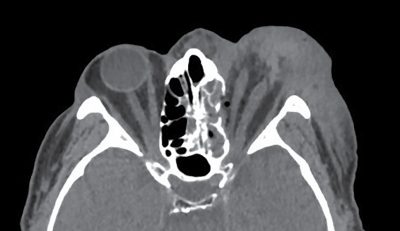

A n. opticus az ellenoldalihoz képest ödémás jelleggel megvastagodott, lefutása a retrobulbaris szakaszt kivéve megtartott, ahol ugyanis folytonossági hiány volt megfigyelhető rajta. A periorbitális zsírszövet kiszélesedett, inhomogénen kitöltött hematómának és ödémának megfelelően (3. ábra).